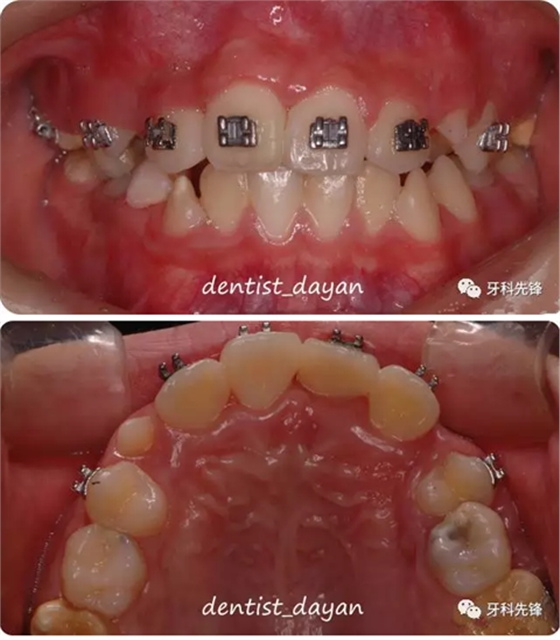

初診時的口內(nèi)照片。